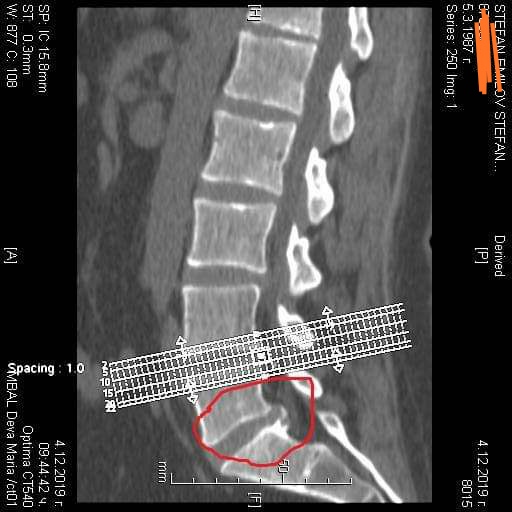

Здравейте. От производителя около месец имам проблеми с кръста. Усложниха се и сега съм с на тибиалния нерв. Болка в кръста нямам но неврохирург и то добър казва да лягам под ножа

Прикачени файлове

IMG_20191218_221550.jpg

IMG_20191218_221550.jpg (67.8 KiB) Прегледано 3323 пъти

Щом имате неврологични симптоми и снимката доказва дискова херния, то е добре да следвате на препоръките на лекаря. Ние трудно можем да дадем някакъв друг съвет.